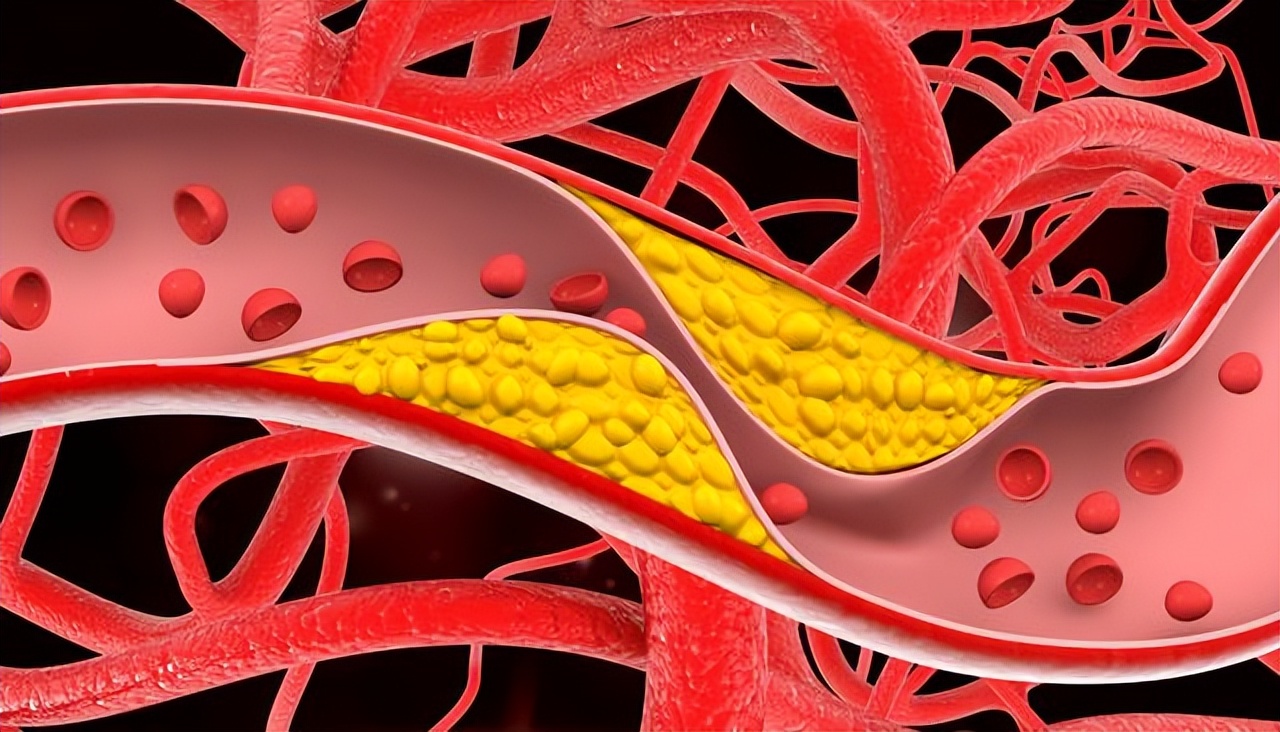

胸不闷、腿不肿,就没事?很多人对“血管堵塞”这四个字没概念,总觉得这是老年人才会得的病,或者只有高血压、高血脂的人才要担心。

更有甚者,体检正常就安心了,忽略了那些藏在生活细节里的预警信号。可血管这东西,堵起来真没声音,等到真出事,往往就是大事。

所以,第一个信号是走路腿疼,尤其是那种走一段疼、休息下又能缓解的,别老想着是缺钙或者劳损,最可疑的是周围动脉硬化闭塞。

其实,阴茎血管是全身最细的动脉之一,一旦血管开始有斑块堵塞,阴茎供血就会最先出问题。所以,男性出现勃起障碍,有时是全身动脉粥样硬化的“哨兵”信号。

说到底,血管堵塞不是一天形成的,它背后是几十年的饮食、作息、情绪积累。症状轻不代表问题小,没症状也不代表没问题。

但血管堵塞从来不是靠“感觉”发现的,那些没症状的堵塞,往往才最致命。心梗发作前80%的冠状动脉患者没有明显症状,这不是猜测,是很多研究反复证实的事实。